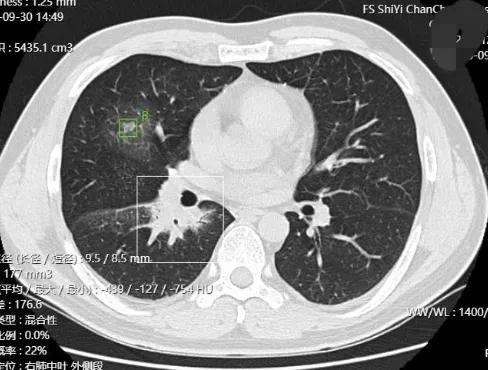

左肺上葉斑片狀混合磨玻璃影,邊緣模糊,收縮乏力,胸膜無明顯影響,總體輪廓比較清楚

右肺中葉以及右肺下葉肺門部,磨玻璃影,也是混合磨玻璃,其中肺門病灶,密度較高